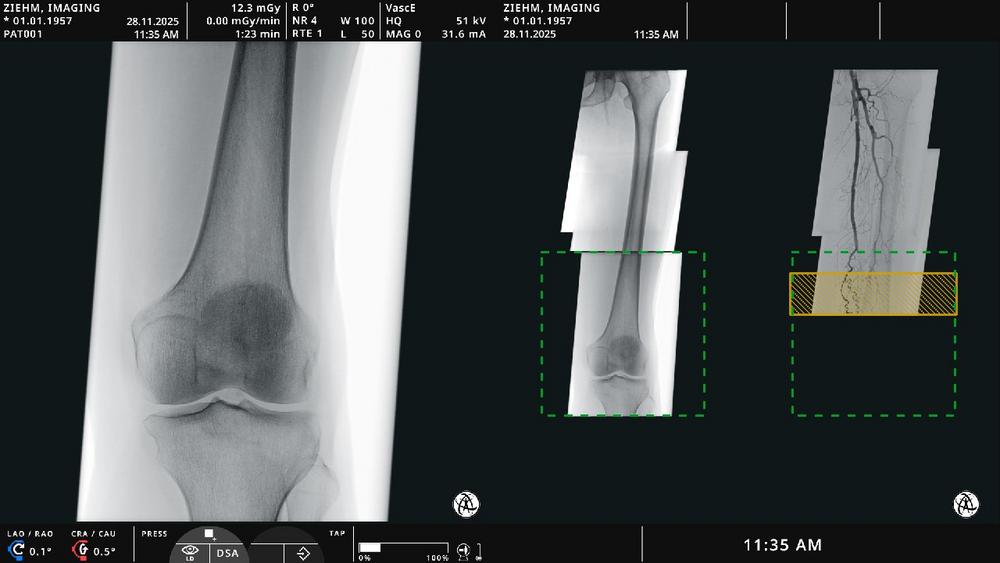

Endovascular Navigation Peripheral ermöglicht die Panorama-Erstellung bei peripheren arteriellen Verschlusskrankheiten, indem Fluoroskopie- und Angiographiebilder zu einer vollständigen, aktuellen Übersicht zusammengefügt werden. Thrombotische und stenotische Bereiche können einfach identifiziert und markiert werden. „Live-Fluoroskopiebilder werden präzise mit dem angiographischen Panorama fusioniert – so können Anwendende mit optimaler Orientierung und ohne zusätzliches Kontrastmittel navigieren“, erklärt Martin Törnvik, Vice President Global Sales & Marketing. Algorithmen auf Basis künstlicher Intelligenz sorgen für automatische Bildfusion. Diese passt sich in Echtzeit an Bewegungen von Patientin bzw. Patient, Tisch oder C-Bogen an. Die Lösung ist vollständig in den Ziehm Vision RFD Hybrid Edition3 (Cardio) und den Ziehm Vision RFD 3D integriert.